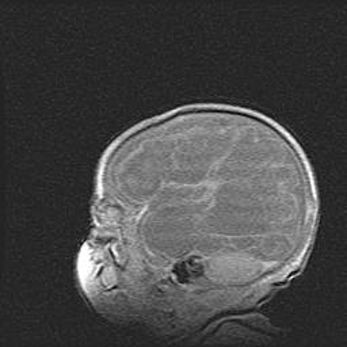

Мальформация Денди-Уокера. Киста задней черепной ямки.

Агенезия мозолистого тела.

Возраст: 2,5 месяца

Вес: 2420 г

Пол: женский

Окружность головы: 37 см

Срок гестации: 32 недели

Мальформация Денди—Уокера — редкий вид патологии ЦНС, представляющий собой врожденный порок развития каудального отдела ствола и червя мозжечка, ведущий к неполному раскрытию срединной (Мажанди) и латеральных (Лушка) апертур IV желудочка мозга. Для этогно синдрома характерна триада симптомов: гипотрофия червя мозжечка и/или полушарий мозжечка, кисты задней черепной ямки, гидроцефалия различной степени. В 70% случаев порок сочетается и с другими аномалиями головного мозга, в частности с агенезией мозолистого тела.